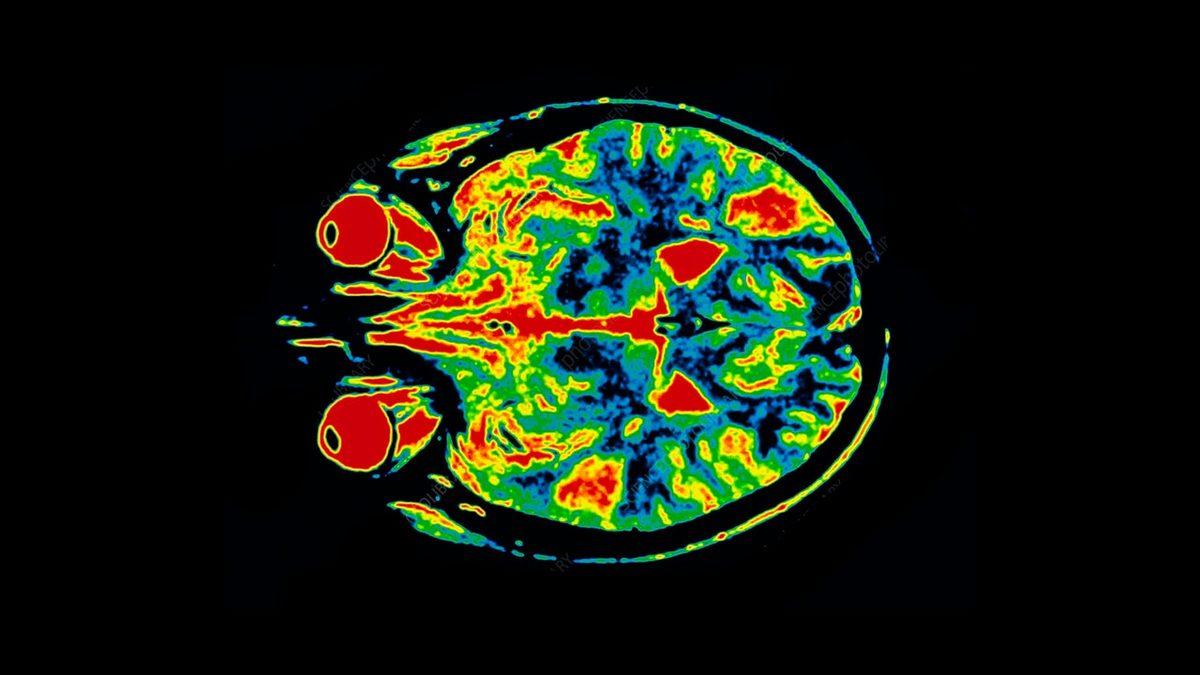

En başında belirtmeliyiz ki hayır, dejà vu bir hastalık ya da hastalık belirtisi değildir. Epilepsi hastalarında bazen nöbetler eşliğinde yaşansa da, hiçbir sağlık sıkıntısı olmayan insanlarda da olabilen dejà vu; beynin işleyişindeki küçük bir anomaliden kaynaklanmaktadır ve söz konusu hissin zaman zaman ortaya çıkması fiziksel ya da ruhsal bir sorununuz olduğu anlamına gelmez. Fakat bu hissiyat düzenli olarak tekrarlanıyorsa bir anormallik olabilir ve acilen bir doktora muayene olmak gerekir.

Yetişkin bireylerde stres, yorgunluk ve benzeri nedenlerden kaynaklanabilen dejà vu, daha ziyade 'epilepsi' hastalarında görülüyor. Nöbet öncesinde, bilinç açıkken ortaya çıkan dejà vu, kişinin daha şiddetli ataklar geçirmesine sebep olabiliyor. Bu nedenle, bilhassa çocukluk ve ergenlik dönemlerinde dejà vu çok sık yaşanıyorsa mutlaka bir doktora başvurulmalı ve epilepsi hastalığı olup olmadığı anlaşılmalıdır.

Bir diğer açıklamaya göre ise beynin sağ lobu ile sol lobu milisaniyeden daha ufak bir zaman farkıyla çalışır ve bunun sonucunda da bir olayı bir taraf daha önce algıladığı için, daha geç algılayan taraf bu olayı daha önce yaşamış gibi olur. Yani başka bir deyişle bu olay, sinir aksonlarındaki küçük bir sapmadan kaynaklanır.

Yapılan araştırmalarda elde edilen bulgulara göre, temporal lob krizleri gelmeden hemen önce dejà vu yaşanabilmektedir. Söz konusu yakınlık, nörolojik düzeyde anomoli oluşturacak elektrik akımlarının deja vuya sebep olduğu neticesini güçlendirmektedir. Ayrıca, dejà vunun Alzheimer hastalığının erken tanısında yararlı olabileceği fikri de öne sürülmektedir. Ancak bu teori şu an için doğruluk kazanmamıştır.

Beyinde meydana gelen minör devre arızaları

Bir diğer teoriye göre de beyniniz ‘hata verdiğinde’ bu, epileptik nöbete benzer bir elektriksel arızaya sebep olur ve bu da dejà vuya yol açar.

Başka bir şekilde anlatmak gerekirse; beyninizin şu anı ve geçmişi kontrol eden kısımları aynı anda çalıştığında beyin hata verir ve dejà vu olursunuz.

Böyle durumlarda beyniniz şimdi olan bir olayı bir ‘anı’ olarak algılar ve o anı daha önce yaşamışsınız hissine kapılırsınız. Bu tarz bir beyin hatası, düzenli olarak tekrarlanmadığı sürece herhangi bir tehlike teşkil etmez.